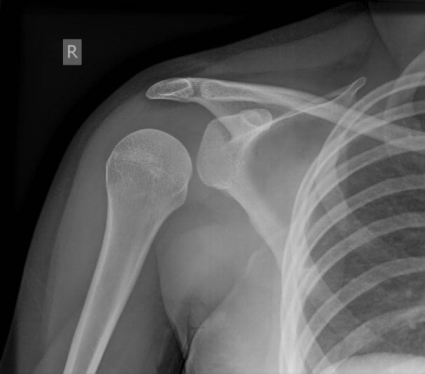

Oh SNAP! Gepost op 5 augustus 20203 augustus 2020 door netwerkvsseh Board Review: Oh SNAP! @emdaily.cooperhealth.org Dit delen: Delen op X (Opent in een nieuw venster) X Share op Facebook (Opent in een nieuw venster) Facebook Delen op LinkedIn (Opent in een nieuw venster) LinkedIn E-mail een link naar een vriend (Opent in een nieuw venster) E-mail Afdrukken (Opent in een nieuw venster) Print Vind-ik-leuk Aan het laden... Gerelateerd